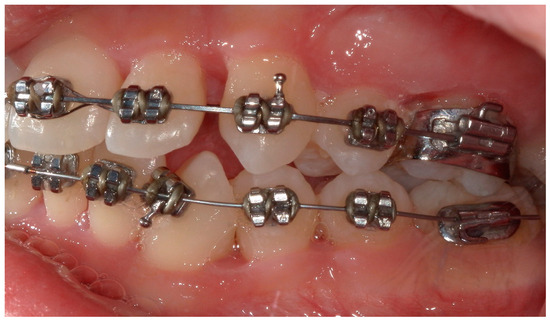

4.1. Case 1